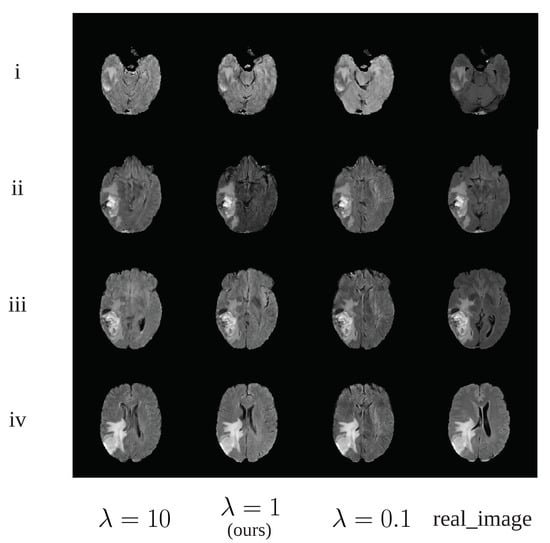

4.3. Qualitative Evaluation